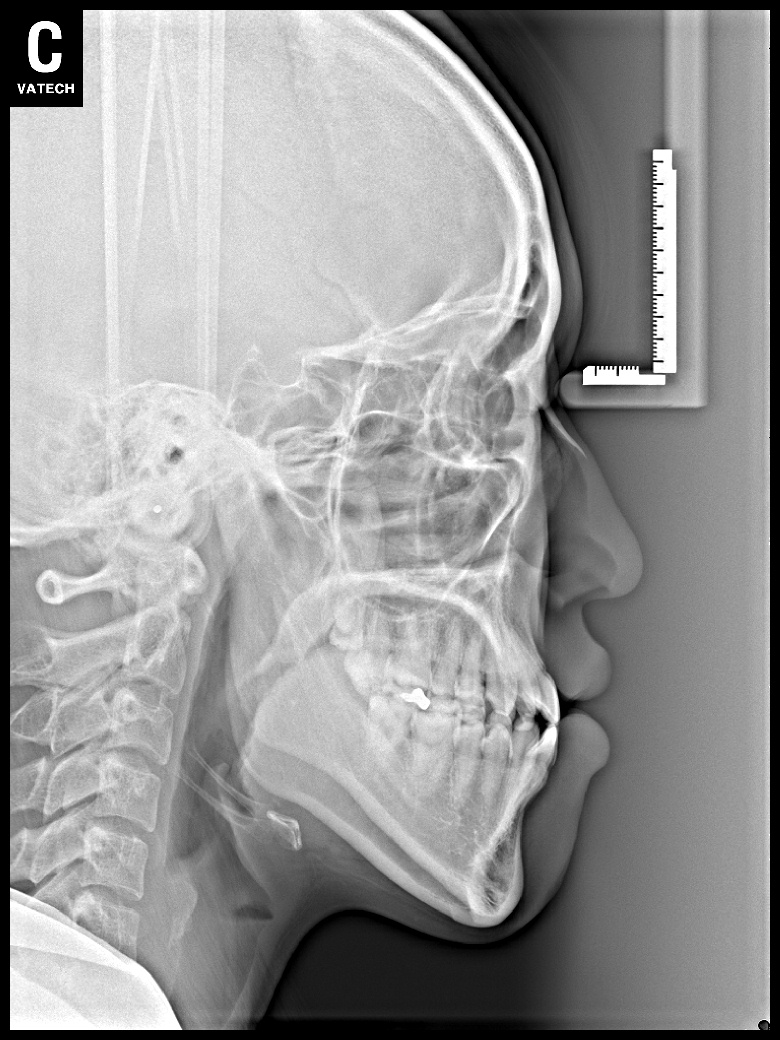

치료 전 사진입니다.